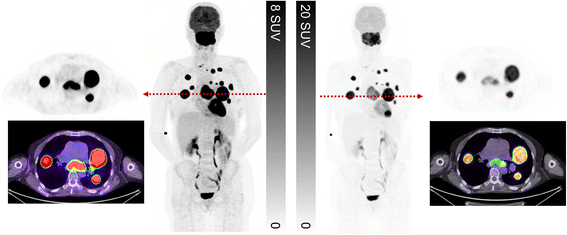

Fig. 7

Patient with non-small cell lung cancer treated with curative intent radiotherapy. Post treatment restaging PET/CT demonstrated a complete metabolic response (ad, c upper SUV threshold adjusted to liver background as detailed above, d upper SUV threshold of 5). Follow-up CT 9 months later demonstrated enlargement of multiple mediastinal nodes considered likely to represent malignant aetiology. Repeat PET/CT (ei) demonstrated low-to-moderate uptake in these nodes. Given the symmetry of distribution in hilar and mediastinal nodes the aetiology was considered inflammatory, which was confirmed by resolution on follow-up. Thresholding the PET with a SUV threshold of 5 (hi) might lead to erroneous description of intense uptake and interpretation as malignant in aetiology